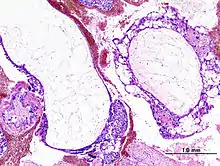

Histopathologic image of hydatidiform mole (complete type). H&E stain.

A hydatidiform mole is a pregnancy/conceptus in which the placenta contains grapelike vesicles (small sacs) that are usually visible to the naked eye. The vesicles arise by distention of the chorionic villi by fluid. When inspected under the microscope, hyperplasia of the trophoblastic tissue is noted. If left untreated, a hydatidiform mole will almost always end as a spontaneous abortion (miscarriage).

Based on morphology, hydatidiform moles can be divided into two types: in complete moles, all the chorionic villi are vesicular, and no sign of embryonic or fetal development is present. In partial moles some villi are vesicular, whereas others appear more normal, and embryonic/fetal development may be seen but the fetus is always malformed and is never viable.

The diagnosis is strongly suggested by ultrasound (sonogram), but definitive diagnosis requires histopathological examination. On ultrasound, the mole resembles a bunch of grapes ("cluster of grapes" or "honeycombed uterus" or "snow-storm").[14] There is increased trophoblast proliferation and enlarging of the chorionic villi, and angiogenesis in the trophoblasts is impaired.[15]